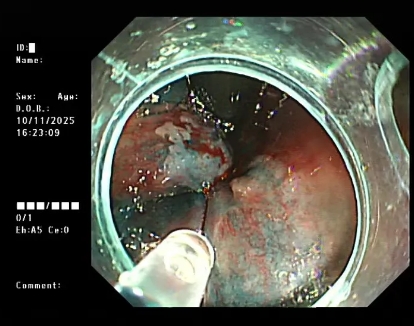

简单说,痔疮硬化治疗就是通过细针将“硬化剂”注射到内痔的黏膜下或痔核内。硬化剂会让痔核周围的组织产生炎症反应,逐渐形成纤维条索,把扩张的血管“扎紧”,同时让痔核萎缩、变小,最终解决便血、脱出等问题。

整个过程不用开刀,创伤特别小,有点像平时打“肌肉针”,多数人不会有明显痛苦。

图片

△内镜下硬化治疗